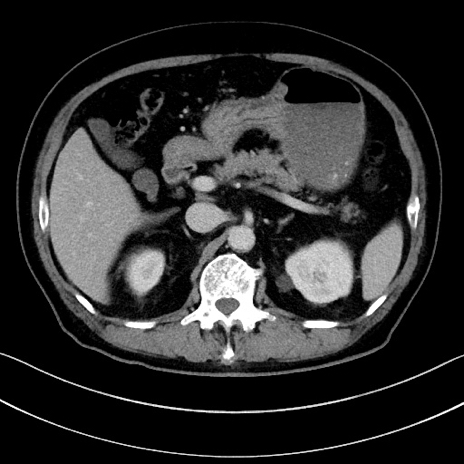

症例15(横断像)

【症例】70歳代男性

【主訴】腹痛

【現病歴】今朝から腹痛あり。全体的に痛い。特に左上の方。排ガスが今日はない。冷や汗が出る。

【既往歴】直腸癌術後

【身体所見】左側腹部〜上腹部に圧痛あり。腹膜刺激症状明らかなではない。軽度反跳痛。左下腹部に術後瘢痕あり。

【データ】WBC 7700、CRP 0.02